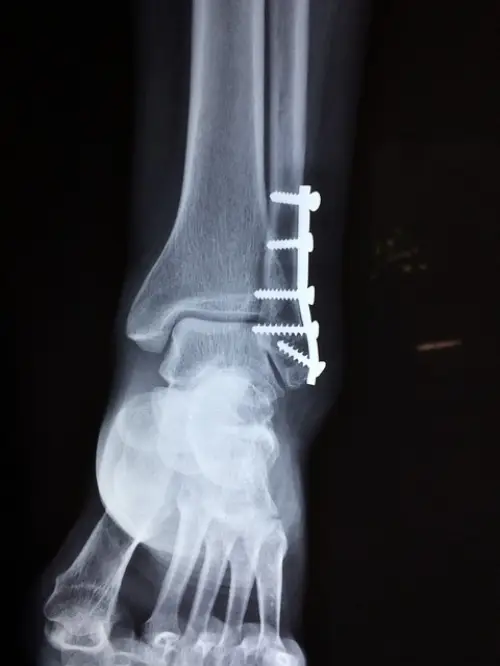

진단에서 영상검사는 필수적입니다. 가장 기본적으로 시행하는 X-ray 검사는 부주상골의 존재 여부, 크기, 형태 및 주상골과의 연결 상태를 확인할 수 있습니다. 특히 부주상골의 분류(1형, 2형, 3형 등)와 증상 발생 가능성을 파악하는 데 필수적입니다.

더 정확한 골조직의 손상이나 미세 골절이 의심될 경우, CT(컴퓨터단층촬영)을 통해 뼈의 세밀한 구조를 확인합니다. 이 검사는 골절 유무뿐 아니라 부주상골과 주변 뼈 사이의 관계를 보다 명확히 해줍니다.

부주상골과 관련된 연부 조직의 상태, 특히 후경골건의 염증이나 파열을 평가하려면 MRI(자기공명영상) 검사가 가장 적합합니다. 연부 조직 변화가 명확히 드러나 치료 방향 결정에 도움이 됩니다. 또한 다른 유사 질환과의 감별 진단에도 MRI는 매우 유용합니다.

| X-ray | 부주상골 존재 확인, 형태 분류 | 기본 영상검사 |

| CT | 미세 골절 및 뼈 구조 정밀 검사 | 필요 시 추가 검사 |

| MRI | 연부조직 염증 및 파열 검사 | 감별 진단에 중요 |

골 유합술은 부주상골과 주상골 사이를 고정하여 두 뼈가 하나처럼 혹은 안정적으로 합쳐지도록 하는 수술입니다. 이 수술은 특히 2형 부주상골, 즉 관절성 연결 부위를 가지고 있어 움직임에 의해 통증이 유발되는 경우에 적합합니다.